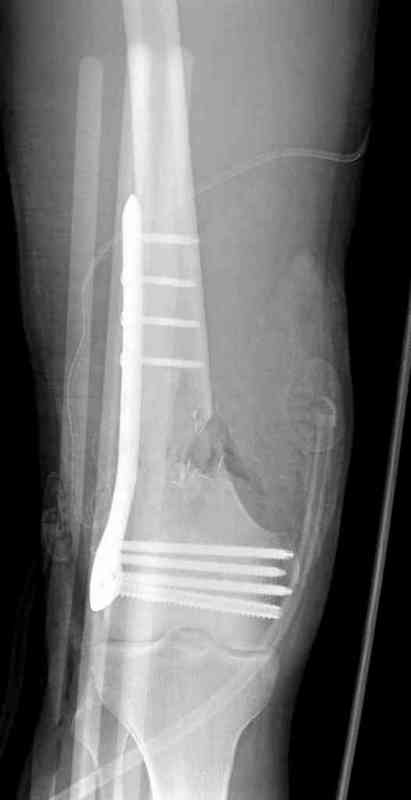

Доступ был латеральный, при вскрытии с задней

поверхности бедра обнаружили кровотечение. Поднятием давления на заранее установленном турникете на конечности проконтролировали кровотечение.

В данном случае мы не ставили осуществление гемостаза приоритетным, после 30 минут больной оставлен вызванному сосудистому хирургу со стабильной фиксацией бедра. Несмотря на выбранный передне-медиальный доступ, хирург произвел восстановление сосудистого повреждения.

Латерально пластину защитили ушиванием

илио-тибиального тракта, а медиальная сторона была ушита мышцей, и все раны закрыли ваккумированием (VAC)

На третий день после Irrigation & Debridment закрыли все раны за исключением компартментальной раны из-за отека, медиально в дефект кости установили Putty Grafton Bone Substitute. На компартментальную рану вакуум и мероприятия по сближению краев раны резиновой стяжкой.

На 9й день с момента травмы ушили рану без натяжения. Больной получает реабилитацию, движения коленного сустава с помощи CPM-continuous passive motion machine. Сегодня выписан.